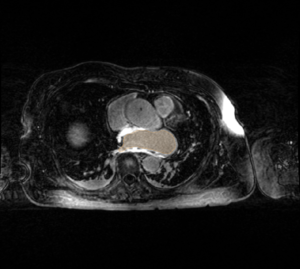

• The CARMA Center uses late gadolinium enhanced MRI (LGE-MRI) images to evaluate new patients, predict procedural success, and evaluate therapeutic outcomes. The MRI images for each patient are further accompanied by MR angiographic images (MRA) and manual segmentations of relevant structures. These images are acquired longitudinally over the course of a patient's evaluation, treatment, and follow-up (i.e. months or years). Registration is often necessary to compare images from different time points in a patient's treatment, different patients at the same stage of disease progression or treatment, and different image types. Registration is needed for a variety of combinations of common image types encountered at CARMA:

MRA Image Immediately Post-ablation LGE-MRI Image CT Image

• MRAs have a bright blood pool, the bounds of which indicate the endocardial surface of the LA wall.

The MRA captures the extent of the blood pool and roughly corresponds to the endocardial surface of the LA wall. The MRA is also much easier to automatically segment. Registration of the MRA to LGE-MRI would allow for segmentation of the MRA blood pool as an initial guess in segmentation of the LGE-MRI blood pool. We will likely need gated MRAs.

MRA to MRA

• Shape-analysis studies -- Image processing group

The MRA is a quick and dirty way of capturing the bounds of the blood pool for shape studies. Alignment of the MRAs will allow for alignment of the blood pool masks for input into shape analysis pipelines (i.e., ShapeWorks)